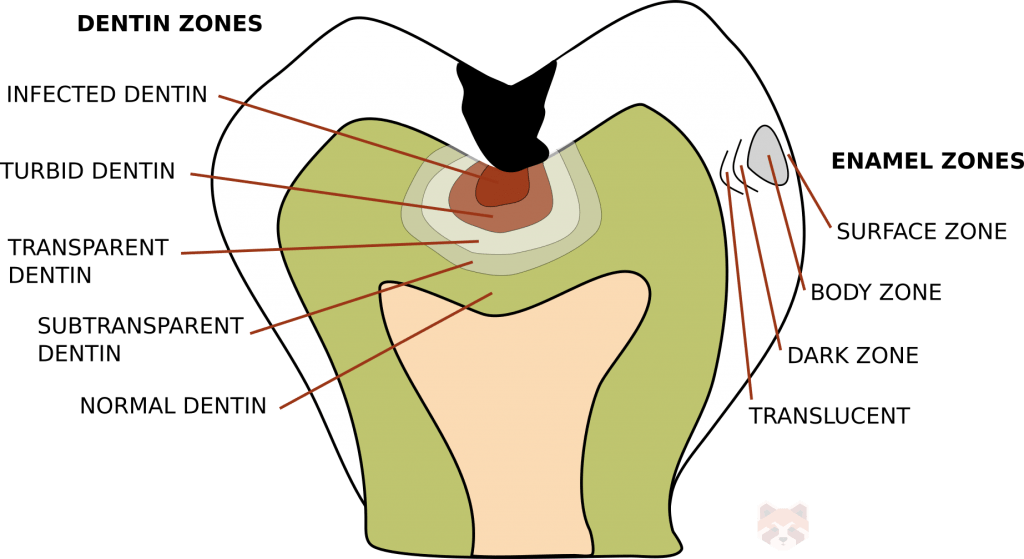

Root surface caries is linked to older patients exhibiting more clinical recession and subsequent root surface exposure. The cementum surface is rougher, thin and less mineralized compared to enamel so plaque adheres to and damages it more readily. Age is also associated with decreased salivary flow (most often due to polypharmacy-induced xerostomia) and inability to clean the teeth well. Recall the zones of carious enamel and dentin:

Enamel

- Translucent zone – faint appearance under polarized light. The advancing front of caries.

- Dark zone – inability to transmit polarized light. Mixed demineralization and remineralization.

- Body zone – the largest zone and the area with the most demineralization.

- Surface zone – seems relatively unaffected.

Dentin

- Normal dentin – no bacteria or byproducts present.

- Subtransparent dentin – demineralization but no bacteria found in dentinal tubules. Affected dentin.

- Transparent dentin – further demineralization, still no/very little bacteria. Affected dentine.

- Turbid dentin – bacteria present in the dentin tubules. Infected dentin. Must remove this zone.

- Infected dentin – many bacteria found in this zone. Infected dentin. Must remove this zone.